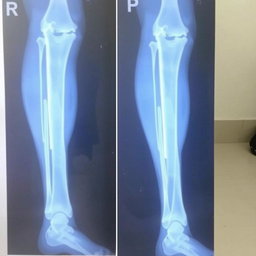

"Make medical report for leg fracture of patient, heading hospital name " national medical college hospital" hospital address: birgunj with given patient details name "Prabesh Kumar Sah" Age "18" and sex "male""